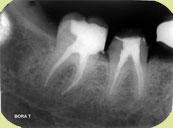

Kanal Tedavisi

Kanal tedavisi dişin içindeki pulpanın temizlenip, bakterilerden arındırılıp, kök ucuna kadar dolgu maddeleri ile doldurularak iltihap sürecinin durdurulması işlemidir. Bazen travma sebebiyle de dişin damar sinir paketi -pulpa- canlılığını kaybedebilir. Böyle durumlarda da kanal tedavisi uygulanır.

Kanal tedavisi lokal anestezikler eşliğinde uygulanan ağrısız bir tedavidir. Damar sinir odası boşaltıldıktan sonra uygun antiseptiklerle yıkanarak kanallar genişletilir. En son aşamada da kanallar kauçuk esaslı dolgu maddeleri ile doldurulur.

Kanal tedavisi bir seansta bitirilebildiği gibi enfeksiyonun fazla olduğu durumlarda pansuman sayısı arttırılarak daha fazla sayıda seans gerektirebilir.